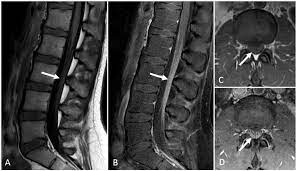

However, it can reveal nerve root enhancement and may be an effective diagnostic adjunct. The severity on mri does not correlate with severity of the clinical condition. Fisher syndrome, a clinical variant of guillain­ barre syndrome characterized by ataxia, are­ flexia, and ophthalmoplegia, brain stem lesions have been described with cranial mr.imaging (8). Its signs and symptoms are similar to those of other neurological disorders and may vary from person to person. Sagittal and axial post contrast t1 fs images shows smooth thickening and abnormal enhancement of the cauda equina and the ventral nerve roots. Moreover, gbs is also associated with any vaccination. Your doctor may then recommend: It is characterized by a triad of ophthalmoplegia, ataxia, and areflexia.

Clinical presentation is usually characterized by rapidly progressive, ascending, and symmetric paralysis of the extremities. Although no abnormalities were observed on brain and spinal magnetic resonance imaging and electroencephalography, peripheral nerve conduction velocity tests failed to evoke motor and sensory nerve action potentials. It is characterized by a triad of ophthalmoplegia, ataxia, and areflexia. Sagittal and axial post contrast t1 fs images shows smooth thickening and abnormal enhancement of the cauda equina and the ventral nerve roots. Scott olson / staff / getty images Moreover, gbs is also associated with any vaccination. Your doctor may then recommend: Mri is sensitive, but nonspecific, for diagnosis. The study findings are published in the journal neurological research. Mr imaging findings in eight patients (three male, five female; Immune checkpoint inhibitors (icis) have been increasingly used in the treatment of various types of tumors with favorable results. The most common result is a weakness and numbness that starts at the tips of the fingers and toes and spreads inward toward the body. Guillain barré syndrome (gbs) is characterized by demyelination and axonal degeneration of peripheral nerves.

Its signs and symptoms are similar to those of other neurological disorders and may vary from person to person. Sagittal and axial post contrast t1 fs images shows smooth thickening and abnormal enhancement of the cauda equina and the ventral nerve roots. Mri is sensitive, but nonspecific, for diagnosis. The diagnosis is usually established on the basis of symptoms and signs, aided by cerebrospinal fluid findings and electrophysiologic criteria. Clinical presentation is usually characterized by rapidly progressive, ascending, and symmetric paralysis of the extremities. Scott olson / staff / getty images Your doctor is likely to start with a medical history and thorough physical examination. It is the most common cause of rapidly progressive flaccid paralysis.

On csf analysis, the cell count is normal in 85% of patients, and high protein values are seen in 64%. Sagittal and axial post contrast t1 fs images shows smooth thickening and abnormal enhancement of the cauda equina and the ventral nerve roots. Clinical presentation is usually characterized by rapidly progressive, ascending, and symmetric paralysis of the extremities. Fisher syndrome, a clinical variant of guillain­ barre syndrome characterized by ataxia, are­ flexia, and ophthalmoplegia, brain stem lesions have been described with cranial mr.imaging (8). Typically, both sides of the body are involved, and the initial symptoms are changes in sensation or pain often in the back along with muscle weakness, beginning in the feet and hands, often spreading to the arms and upper body. Mr imaging findings in eight patients (three male, five female; With treatment, people may improve more quickly. However, it can reveal nerve root enhancement and may be an effective diagnostic adjunct. Your doctor may then recommend: The most common result is a weakness and numbness that starts at the tips of the fingers and toes and spreads inward toward the body. Moreover, gbs is also associated with any vaccination. Mri is sensitive, but nonspecific, for diagnosis. Immune checkpoint inhibitors (icis) have been increasingly used in the treatment of various types of tumors with favorable results.